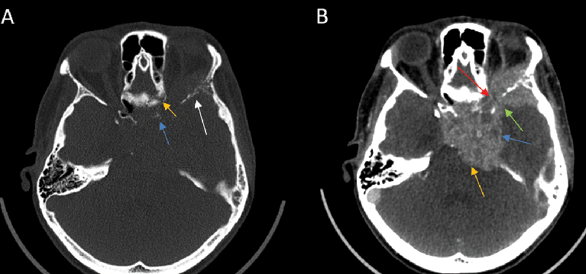

1) PNS commonly presents as enhancement of the affected nerve, which is attributed to the disruption of the blood-nerve barrier caused by the tumor growth and the associated nerve damage [28]. This enhancement is frequently accompanied by nerve enlargement due to multiple pathophysiological processes including tumor infiltration, inflammation, interstitial edema, and neurotrophic factor-induced hypertrophy [1]. However, in some instances, enhancement may occur without appreciable nerve enlargement, thus creating diagnostic challenges in radiological detection. Magnetic Resonance Imaging (MRI) optimally demonstrates both neural enhancement and enlargement, particularly when extending through neural foramina. Pathologic enhancement is characterized by diffuse, uninterrupted enhancement with no clear demarcation from the Perineural Vascular Plexus (PNVP) (Fig. 1, A, B and C) [2]. Careful evaluation of the enhancement intensity, thickness, and symmetry between the sides is essential to identify pathological changes. On CT, although individual nerves may not be well-defined, excessive contrast enhancement in neural foramina or canals can indicate nerve involvement [29].

2) Enlargement and/or Erosion of Neural Foramina or Canals (Figs. 2–3). Perineural Spread (PNS) can manifest radiologically as morphological alterations of neural passageways, characterized by foraminal or canal enlargement secondary to neural expansion. This is a delayed finding, as the normal nerve is smaller than the foramen, and it has ample time to enlarge before bone destruction becomes evident. On imaging studies, this enlargement of foramina typically presents as bilateral asymmetry. However, isolated foraminal enlargement demonstrates limited specificity, as it may represent benign pathological processes or anatomical variants. The presence of concurrent foraminal or canal erosive changes provides stronger radiological evidence for malignant processes, particularly PNS, thereby carrying greater diagnostic significance [29]. Enlargement or erosion of neural foramina or canals is more effectively visualized on CT compared to MRI.

4) On CT or MR imaging, replacement of the fluid signal in Meckel’s cave by a solid and enhancing lesion (Fig 1 C) indicates invasion of the trigeminal cistern [29].

5) On CT and MRI, cavernous sinus invasion is characterized by enlargement of the cavernous sinus, with lateral bulging and increased convexity. However, on CT, it can be challenging to distinguish the enhancing tumor tissue from the venous-filled cavernous sinus on T1-enhanced sequences. [30].